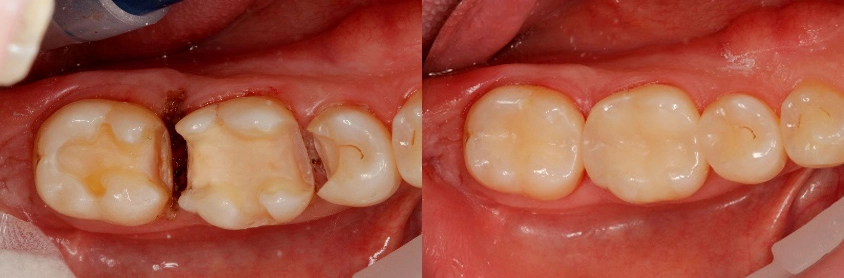

Restaurationen aus Tetric CAD lassen sich schnell im CEREC MCXL-Gerät mit den üblichen diamantierten Schleifern bearbeiten. Die Oberflächen werden mit handelsüblichen Composite-Polieren, z.B. OptraPol in sehr kurzer Zeit auf Hochglanz poliert.

Hochleistungs-Composite werden lege artis nach dem bewährten adhäsiven Befestungsprotokoll auf Schmelz und Dentin verklebt. Zur Konditionierung der Composite-Oberfläche wird diese zuvor mit 50 mµ AlO2 angestrahlt. Nach dem Konditionieren mit Adhese® Universal werden sie z. B. mit Variolink® Esthetic adhäsiv eingegliedert.